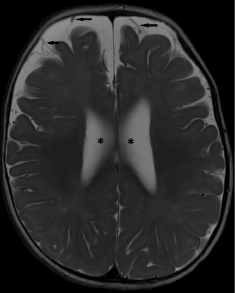

• Thirdly, one should be aware of the presence of terminal zones of myelination at the peritrigonal regions. These should not be mistaken for periventricular leukomalacia [21]. A thin rim of normally myelinated T2 hypointense white matter may be seen between the ependymal surface and terminal zone of myelination, a useful clue to search for [22]. High T2 signal related to terminal zone of myelination is also almost always confined to the supero-posterior aspects of the posterior horns [23,24]. Another helpful clue is the triangular configuration of the terminal zones of myelination on coronal images, with the apex of the triangle directed superiorly [25] (Figure 3 a-c).

• Figure 3. (a) Axial T2-weighted and (b) coronal FLAIR images show the normal terminal zone of myelination, posterior and superior to the occipital horns. Note the triangular configuration of the terminal zones of myelination on coronal image, with the apex of the triangle directed superiorly. (c) Axial T2-weighted image shows abnormal periventricular T2 hyperintense signal extending anteriorly around the bodies of the lateral ventricles, in a child with periventricular leukomalacia.

Figure 3. (a) Axial T2-weighted and (b) coronal FLAIR images show the normal terminal zone of myelination, posterior and superior to the occipital horns. Note the triangular configuration of the terminal zones of myelination on coronal image, with the apex of the triangle directed superiorly. (c) Axial T2-weighted image shows abnormal periventricular T2 hyperintense signal extending anteriorly around the bodies of the lateral ventricles, in a child with periventricular leukomalacia.